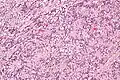

| Micrograph of an intranodal palisaded myofibroblastoma. H&E stain. | |

IPMs are diagnosed by examination of the tissue by a pathologist. They have a rim of peripheral lymphoid tissue (remnant of a lymph node) and consist of spindle cells with nuclear palisading. Red blood cell extravasation is common and blood vessels surrounded by collagen with (fine) peripheral spokes (amianthoid fibers) are usually seen.[2]

Immunostains for smooth muscle actin and cyclin D1 are characteristically positive. The main histologic differential diagnosis is schwannoma.

Low mag.